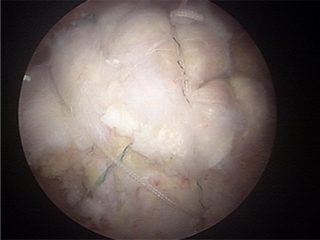

수술 후

• 의료진소개